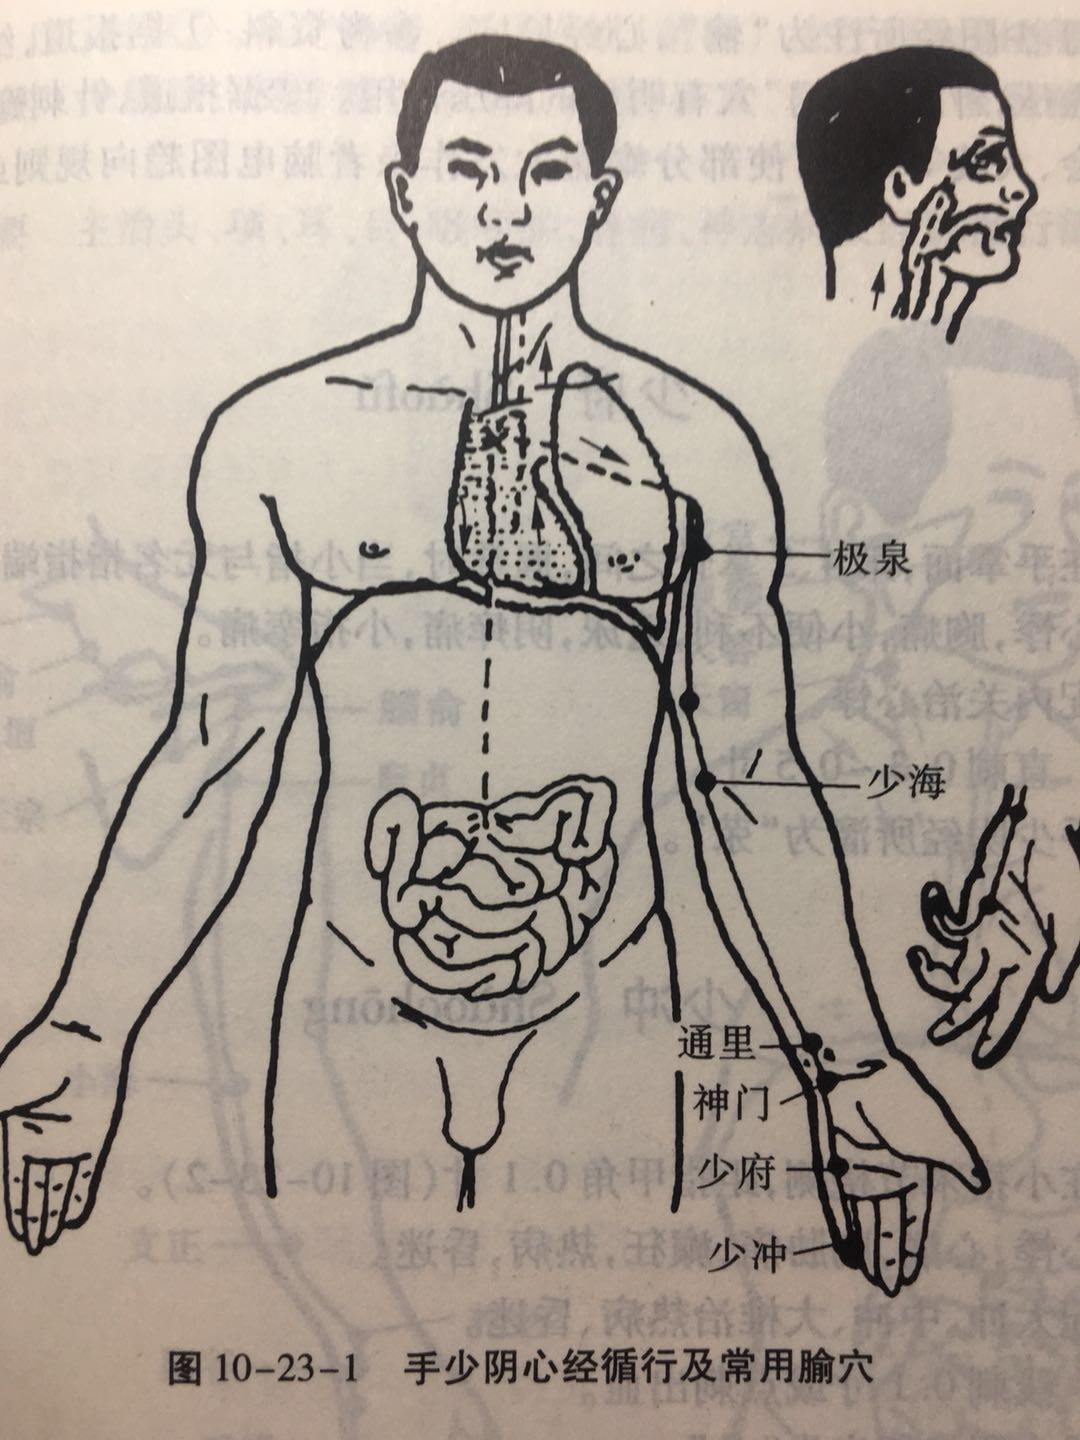

【(五)手少阴心经(图10-23-1)】

1、时辰 午时 11 ~ 13

2、歌诀 手少阴心起极泉,青灵少海灵道全,通里阴郗(chī)神门下,少府少冲小指边。

3、经脉循行 起于心中,出属心系(心与其他脏器相连的部位),过膈,联络小肠。“心系”向上支脉:夹咽喉上行,连于目系(眼球连于脑的部位)。

“心系”直行的脉:上行于肺部再向下出于腋窝部(极泉),沿上臂内侧后缘,行于手太阴和手厥阴经的后面,至掌后腕豆骨部入掌内,沿小指内侧至末端(少冲)交于手太阳小肠经。

4、主要病候 心痛、咽干、口渴、目黄、胁痛、上臂内侧痛、手心发热等。

5、主治概要 主治心、胸、神志病及经脉循行部位的其他病证。

少海

【定位】 屈肘,当肘横纹内侧端与肱骨内上髁(kē)连线的中点处。

【主治】 心痛,肘臂挛痛,瘰疬,头项痛,腋胁痛。

【配伍】 配曲池治肘臂挛痛。

【刺灸法】 直刺 0.5 ~ 1 寸。

【附注】 手少阴经所入为“合”。

神门

【定位】 在腕部,腕掌侧横纹尺侧端,尺侧腕屈肌腱的桡侧凹陷处。

【主治】 心病,心烦,惊悸,怔忡,健忘,失眠,癫狂痫,胸胁痛。

【配伍】 配内关、心俞治心痛,配内关、三阴交治健忘、失眠。

【刺灸法】 直刺 0.3 ~ 0.5 寸。

【附注】 手少阴经所注为“输”,心经原穴。参考资料:①据报道,给狗注射垂体素造成垂体性高血压,针刺“神门”穴有明显的降压作用。②据报道,针刺癫痫病人的神门、阴郗、通里、百会、大陵等穴,可使部分癫痫大发作患者脑电图趋向规则或使病理性脑电波电位降低。

少府

【定位】 在手掌面,第 4、5 掌骨之间,握拳时,当小指与无名指指端之间。

【主治】 心悸,胸痛,小便不利,遗尿,阴痒痛,小指挛痛。

【配伍】 配内关治心悸。

【刺灸法】 直刺 0.3 ~ 0.5 寸。

【附注】 手少阴经所溜为“荥(yíng)”。

少冲

【定位】 在小指末节桡侧,距指甲角 0.1 寸(图 10-23-2)。

【主治】 心悸,心痛,胸胁痛,癫狂,热病,昏迷。

【配伍】 配太冲、中冲、大椎治热病、昏迷。

【刺灸法】 浅刺 0.1 寸或点刺出血。

【附注】 手少阴经所出为“井”。